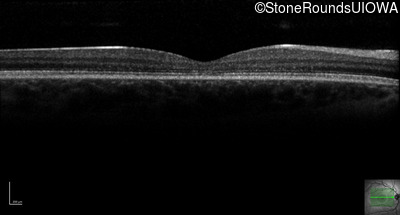

Optical Coherence Tomography - Left - 20/125

Exemplar / OCT Stack